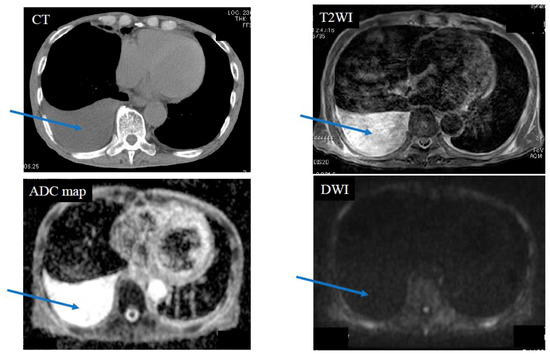

| Pleural effusion | 0 | 0 | 0 | 12 | 12 | |